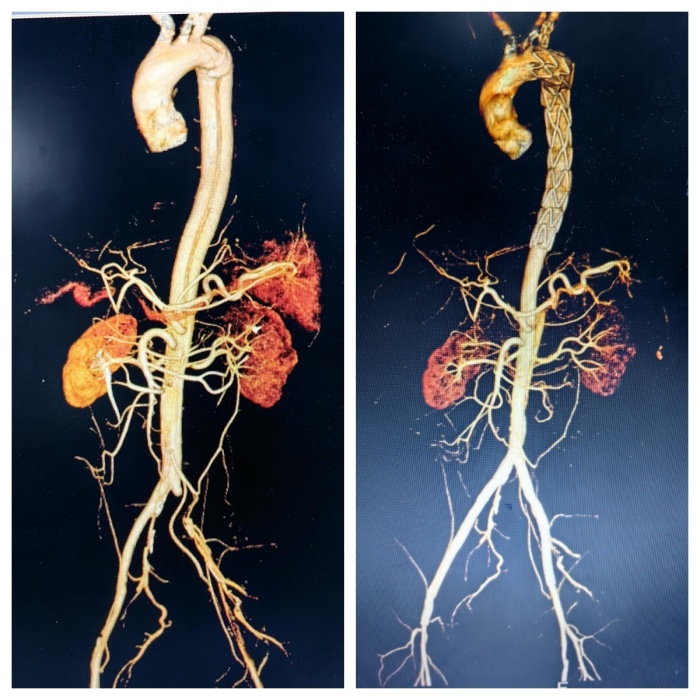

(图片4:术前术后三维对比)

手术一结束,胡某冰冷的左下肢马上就变得暖和起来了,疼痛也明显缓解,术后第2天下肢感觉及活动逐渐恢复正常,并能自行下床活动,术后1周复查良好,顺利出院。

然而,医生们并未退缩,他们凭借着丰富的经验和精湛的技术,另辟蹊径,从上往下成功找到真腔,并顺利完成了手术。在胸主动脉近端置入覆膜支架一枚,覆盖内膜破口;开通闭塞的左髂总动脉并置入支架;右髂动脉细小真腔内也成功置入支架。手术成功封堵住主动脉内膜破口并恢复下肢供血,挽救了胡某的生命并保住了他的下肢。